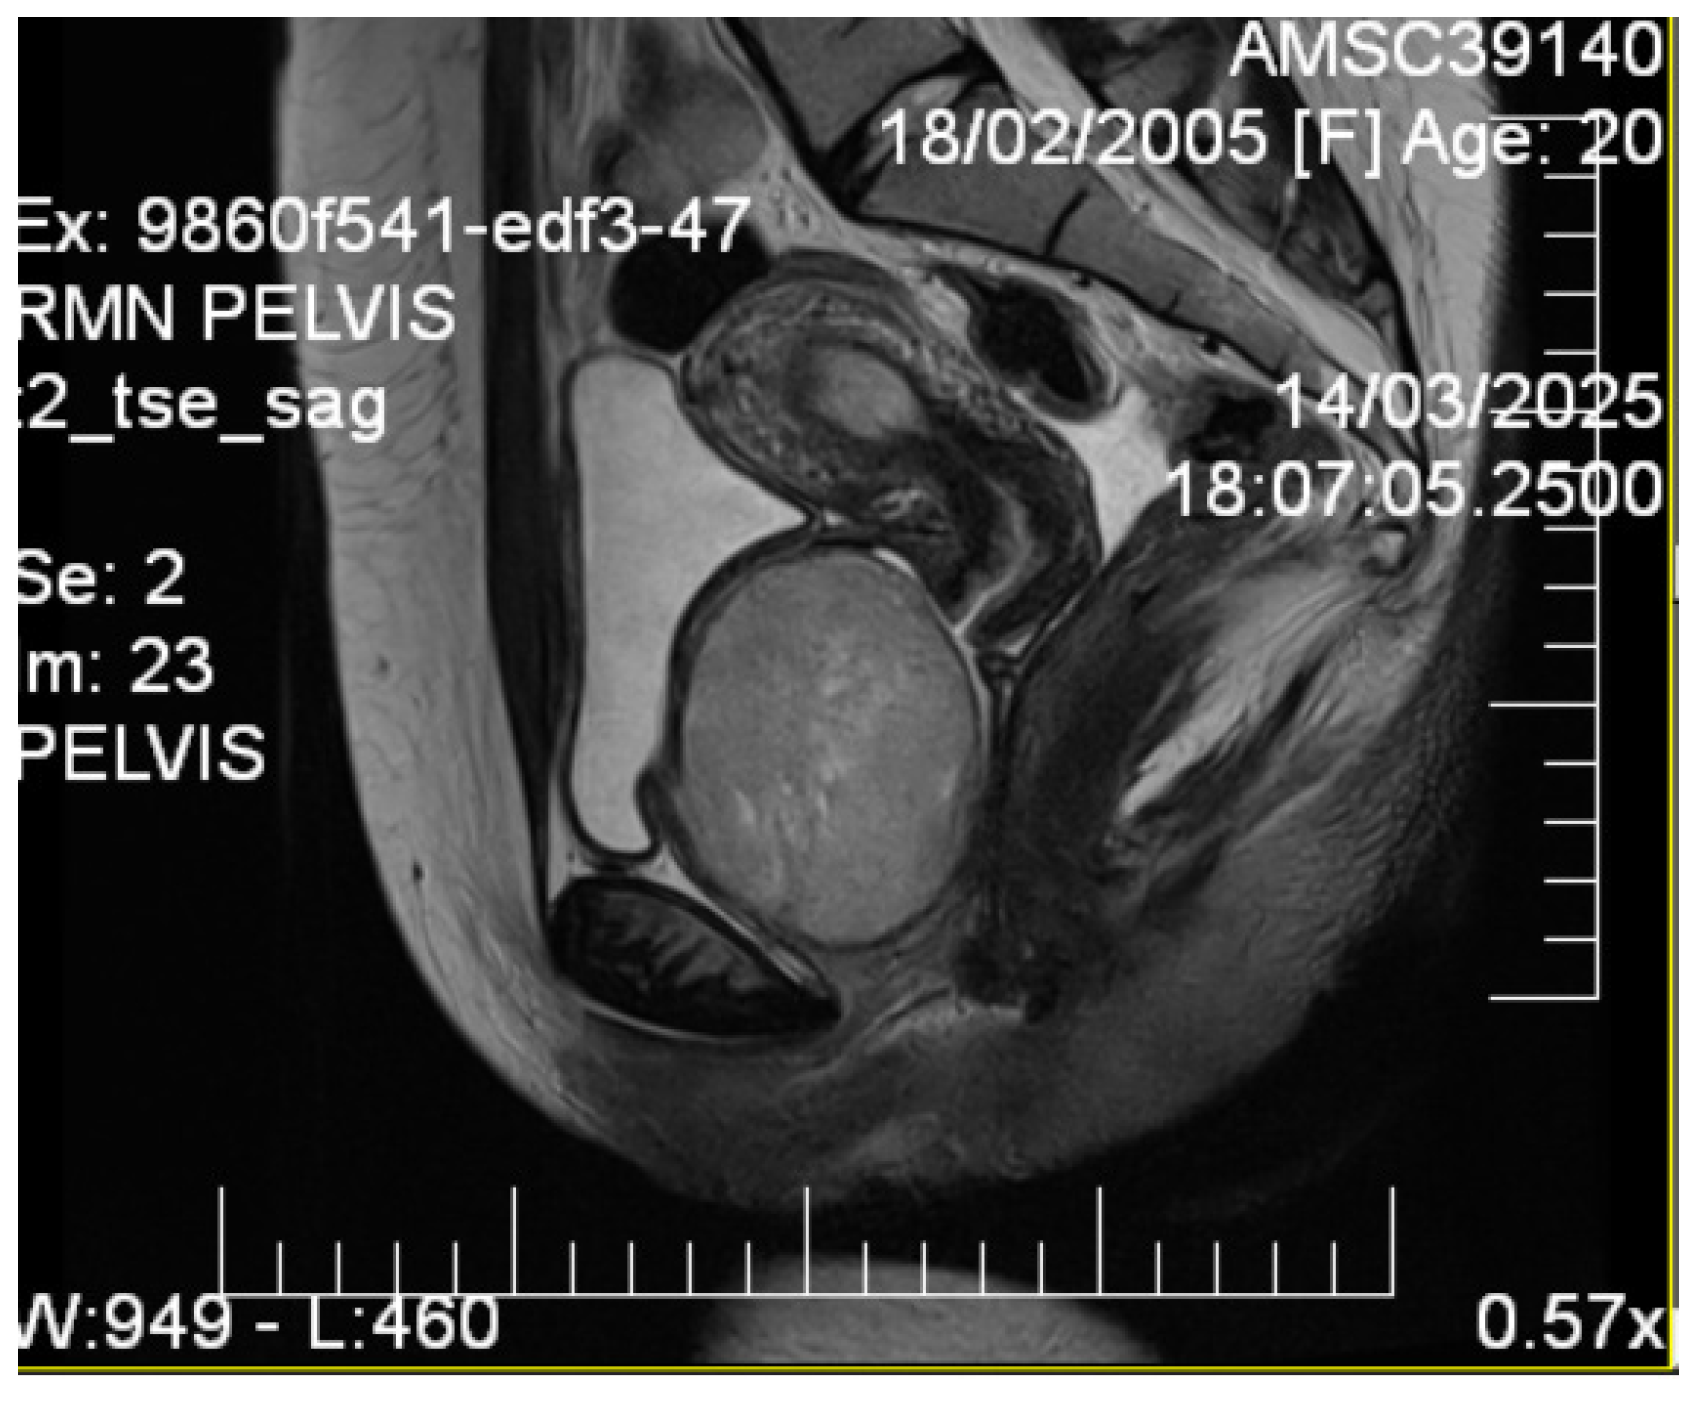

2.4. Imaging Studies

3.1. Imaging Characteristics and Diagnostic Precision

- MRI is decisive in characterizing tissues.